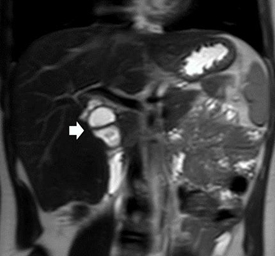

No other symptoms and signs were associated during “attacks”. Laboratory tests were always normal during the episodes. During a new episode (9 year-old) other ultrasound was performed. A cyst was observed in the hepatic hilum and the gallbladder fossa was apparently empty (Figure 1: A, B). Trying to clarify the anatomy a CT-scan was perfomed and an upper gastrointestinal contrast study to rule out a duodenal duplication cyst. Again other Magnetic Resonance Cholangiopancreatography (MRCP) was accomplished (Figure 2).

Figure 2 Coronal MRCP T2 image shows a cystic ductal formation in the hepatic hilum (arrow) suggestive of a choledochal cyst.